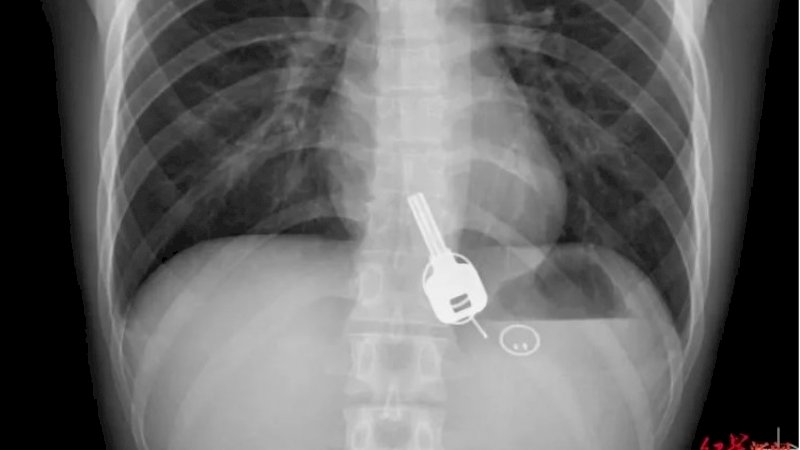

Ketika dokter melakukan rontgen, mereka terkejut melihat apa yang tampak seperti kunci yang bersarang di kerongkongannya.

Mereka bertanya kepadanya tentang hal itu, dan dia mengaku kehilangan kunci rumahnya pada malam sebelumnya, tetapi tidak bisa memberikan penjelasan bagaimana benda itu bisa masuk ke dalam tubuhnya.

Menurut situs berita China, Sohu, dia sama terkejutnya dengan para dokter ketika dia melihat X-ray.